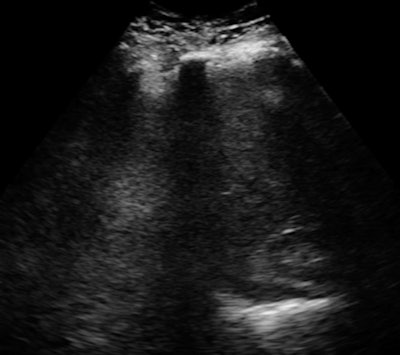

Rather than target low-end or midrange ultrasound, InnerVision has set its sights high, preferring to compare its technology to the best super-premium systems from major ultrasound vendors.

The firm has also picked the toughest patients: obese individuals for whom ultrasound has difficulty. In clinical validation studies, the InnerVision technology has been able to demonstrate anatomical structures deep in the body in patients with body mass indexes as high as 66. By showing its expertise in these patients, InnerVision should be able to excel in any other area, the company believes.